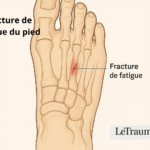

Microtraumatismes liés au sport ou à la marche prolongée

Les activités sportives intensives (course à pied, danse, randonnée) ou la marche prolongée provoquent des microtraumatismes répétés. Ces chocs répétés irritent la bourse et favorisent l’inflammation.

Bursite plantaire et appuis répétés

Sous l’avant-pied, les appuis excessifs et les sports d’impact peuvent enflammer les bourses plantaires. Cette forme entraîne des douleurs lors de la marche et peut gêner le port de chaussures.

Bursite inter-métatarsienne et chaussage étroit

Cette bursite survient entre les os du pied, souvent à cause de chaussures trop serrées comprimant l’avant-pied. Elle provoque une douleur localisée entre les orteils et une gêne lors de la marche.